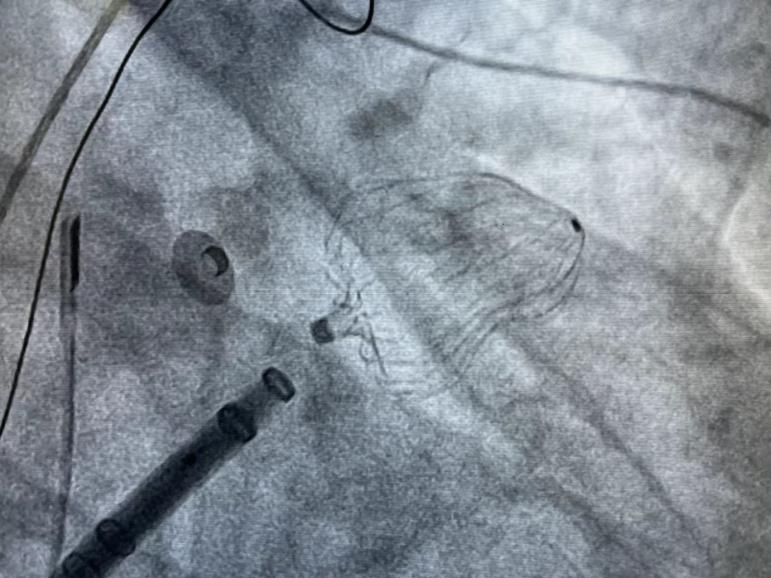

此例手术由韩稳琦博士和酉鹏华博士通过ICE指导下进行,通过ICE精准构建心脏模型、直视下穿刺房间隔,结合三维标测系统,精准、高效地完成双侧肺静脉隔离。后通过ICE及左心耳造影评估左心耳特征为下缘短,上缘折角大的短颈鸡翅型心耳,利用12F导引系统鞘管和猪尾导管在DSA肝位下同时造影,测量左心耳开口25.12mm,最大可用锚定区深度19.71mm,最终选择31mm规格watchman FLX封堵器的植入。ICE从不同角度检查即将释放的WATCHMAN FLX左心耳封堵器,观察封堵器位置、露肩、残余分流和压缩比情况,明确封堵器位置合理,无明显露肩,完全封堵无残余分流,封堵器位置良好。随后在ICE下观察及DSA透视下作牵拉试验,直到最后一次牵拉与前一次牵拉比较无位置改变,压缩比无明显变化,符合封堵器释放的“PASS”原则后完全释放封堵器。

图4 Watchman FLX封堵器释放